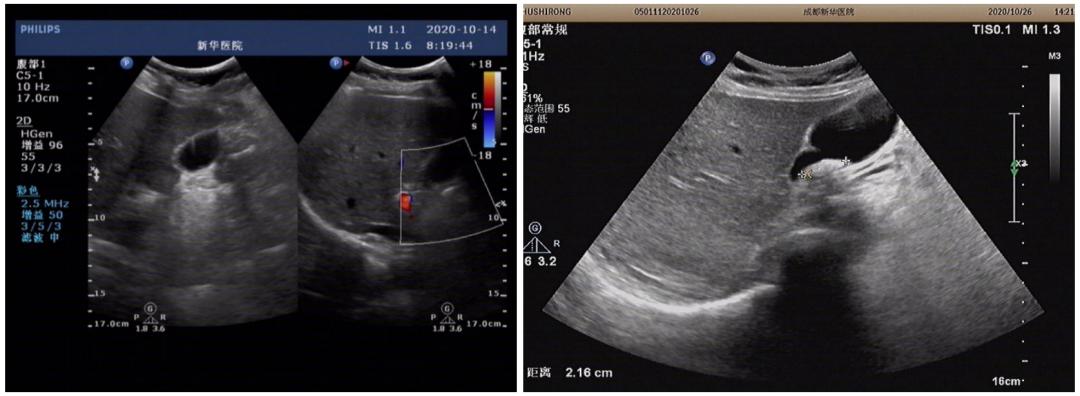

后期胃镜检查:慢性非萎缩性胃炎伴黏膜糜烂,但住院后10天,患者进食油腻食物后突发剧烈上腹部疼痛,立即复查腹部彩超后示:胆囊大小形态正常,壁厚约0.4cm,囊内可见最大约0.8cm的强回声团伴声影。

胆道:肝外胆管上段内径0.6cm,肝内胆管不扩张,胰腺形态大小正常,实质回声均匀,胰管不扩张。

MRCP:胆囊体积缩小,壁增厚,周围液体聚集,胆囊内见点状充盈缺损影,胰腺及脾脏形态大小及信号未见异常,考虑结石性胆囊炎,胆囊周围少量积液。

两名患者,均是在入院后先后间隔1周左右复查腹部彩超或者MRI提示新发胆囊结石,是医技科室漏诊,还是其他因素所致短期内新发结石呢?

请彩超室高年资医生对比前后两次彩超图片,亦提示第一次检查未见确切结石影,第二次却见明显结石影,排除彩超误诊可能。

从患者用药入手考虑后发现两名患者均有长时间使用相同药物头孢曲松钠抗感染治疗,且使用剂量都为2g每天一次。查阅相关文献后,考虑头孢曲松钠所致的假性胆囊结石。